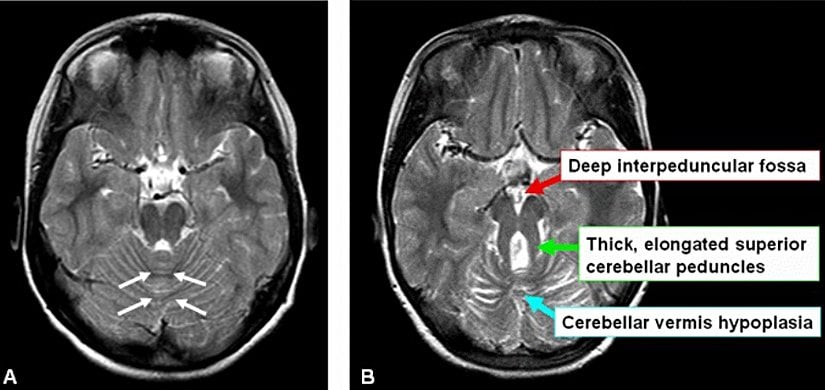

Joubert sendromu, beynin arka kısmında bulunan beyincik yapılarındaki, cerebellar vermis'te ve beyin sapındaki anormal gelişmelerden kaynaklanan ve molar diş belirtisi olarak adlandırılan beyin anomalilerinin bir kombinasyonu ile tanımlanır. Molar diş belirtisi (figür 1) MRI gibi beyin görüntüleme sistemleri ile görüntülenebilir. Bu belirti MR görüntülerinde azı dişine benzediğinden dolayı “molar tooth” olarak adlandırılmıştır.